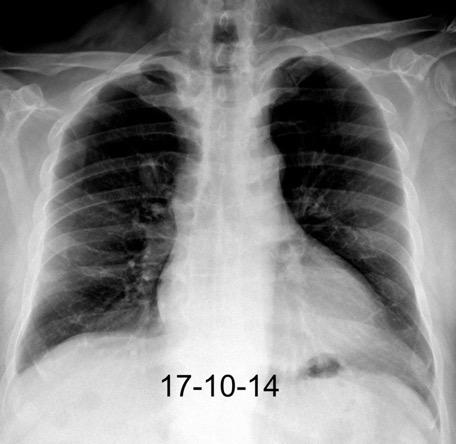

Marzo 2014: Perforación longitudinal distal secundaria a episodio de vómito (síndrome de Boerhaave). Derrame pleural izdo. que evoluciona a empiema.

Wang C-T et al. Tension hydropneumothorax in a Boerhaave syndrome patient: A case report . World J Emerg Med, 2021. Katabathina V et al. Nonvascular, nontraumatic mediastinal emergencies in adults:a comprehensive review of imaging findings. Radiographics. 2011.